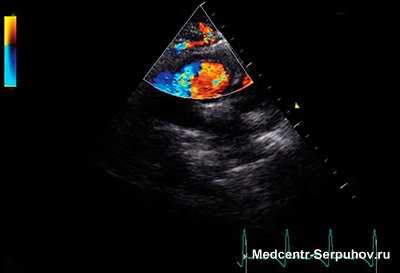

Если по какой-либо причине створки митрального клапана не могут полностью закрыть митральное отверстие, во время систолы левого желудочка кровь устремляется через щель под действием большой разности давлений между желудочком и предсердием. Брешь между створками клапана действует как локальное сужение, через которое кровь бьет струей с высокой скоростью в камеру левого предсердия. При этом возникает турбулентность, вызывая систолический шум.

Шум митральной недостаточности при приобретенных пороках обычно большой интенсивности, особенно у больных с сохраненной сократительной способностью левого желудочка. Этому способствует большая скорость регургитационной струи, которая дает высоко амплитудные вибрации турбулентного тока крови. В связи с постепенным уменьшением давления в левом желудочке при его опорожнении и ростом давления в левом предсердии при его заполнении кровью градиент давления между левыми камерами сердца снижается, что приводит к уменьшению скорости регургитации и к снижению амплитуды вибраций турбулентного кровотока. Следовательно, громкость систолического шума на его продолжении будет уменьшаться. Такие уменьшающиеся по громкости шумы называются убывающими (decrescendo).

Систолический шум — наиболее важная объективная находка. Его следует отличать от систолического шума аортального стеноза, ТР и ДМЖП. У большинства пациентов с тяжелым МР систолический шум начинается сразу после мягкого S1, продолжается дальше и может перекрывать А2 из-за сохраняющегося различия давлений в ЛЖ и ЛП после закрытия АК. Голосистолический шум хронической МР обычно постоянный, дующий, высокочастотный и наиболее громкий на верхушке с частой иррадиацией в левую подмышечную и левую подлопаточную области.